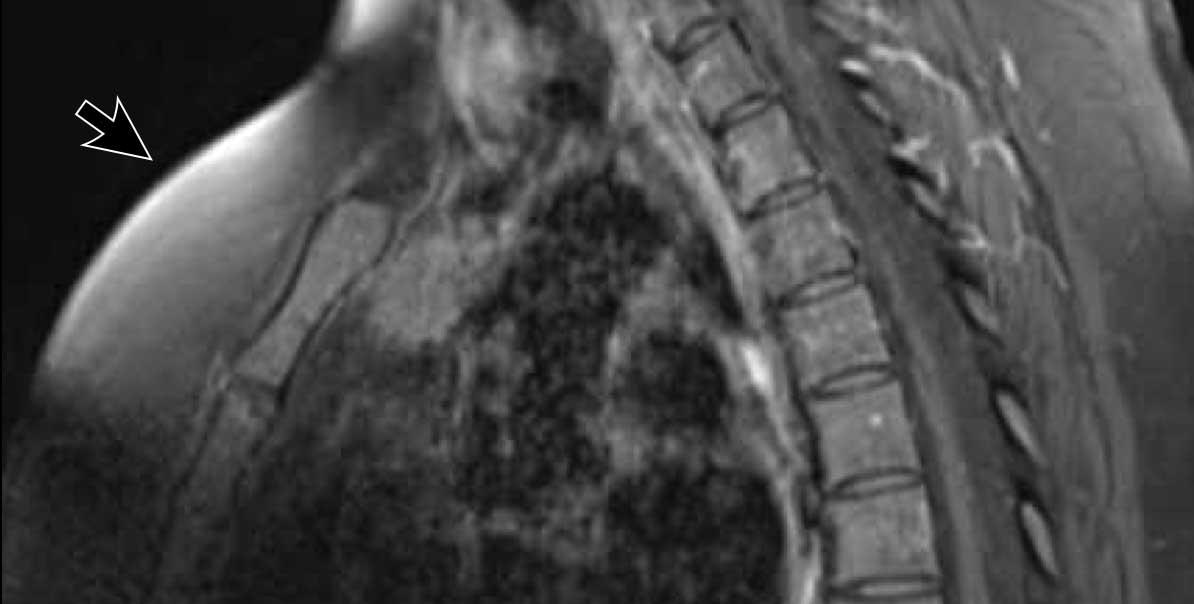

Các hình ảnh này của một bệnh nhân nam 36 tuổi bị hội chứng Cushing, đã được phẫu thuật cắt bỏ u tuyến yên.

Tuy nhiên, hội chứng Cushing vẫn tồn tại và phát hiện một khối ở trung thất.

Hình ảnh

Khối đặc với vôi hóa trung tâm (mũi tên đen).

Lưu ý bờ khối không đều ở phía bên trái.

Hạch bạch huyết thượng đòn trái to (hạch Virchow: mũi tên trắng).

Đây không phải là PET-CT thông thường mà là PET Dotatoc, được sử dụng để phát hiện u thần kinh nội tiết và các tổn thương di căn của chúng.

Có nhiều tổn thương di căn xương (mũi tên).

Chẩn đoán cuối cùng

U thần kinh nội tiết tuyến ức (NETT)

U thần kinh nội tiết tuyến ức là các u hiếm gặp.

Chúng có tính chất rất xâm lấn và thường biểu hiện với sự xâm lấn các cấu trúc trung thất xung quanh, đồng thời liên quan đến các bệnh lý nội tiết như hội chứng Cushing, to đầu chi (acromegaly) và hội chứng MEN-1.